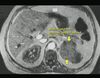

RAK KORY NADNERCZY

TK